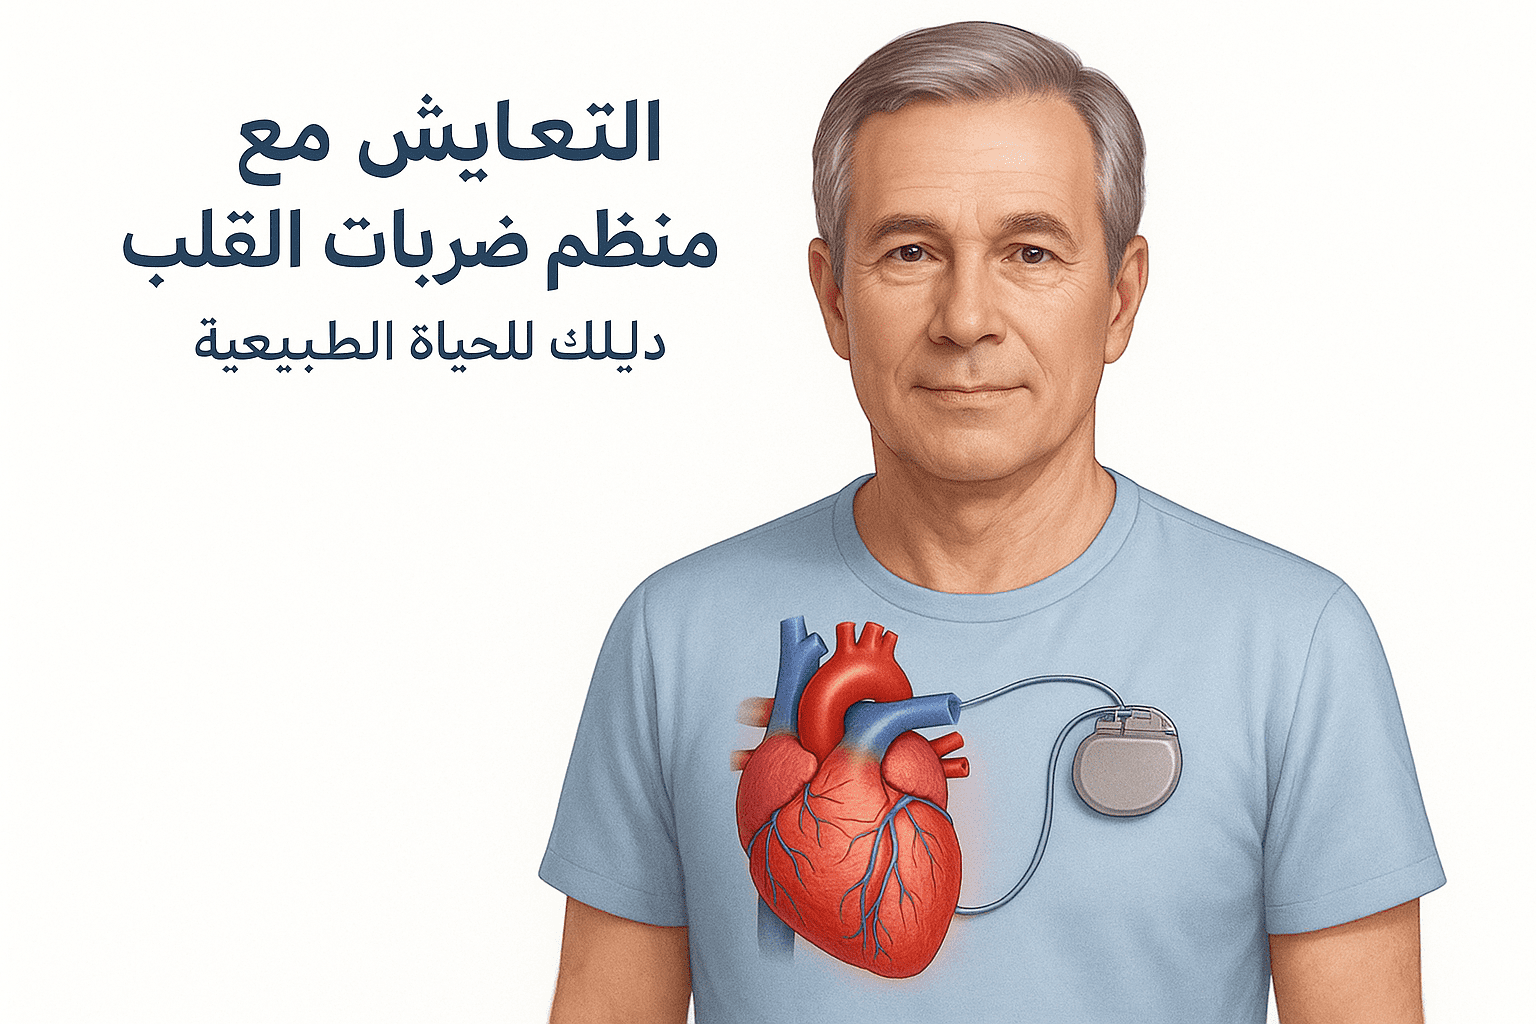

مقالات طبية من مساهمات الأطباء